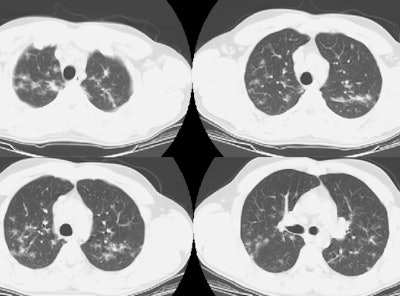

The lung windows revealed the presence of ill-defined nodular densities predominantly in the upper lobes. The patient was presumed to have metastatic testicular carcinoma, but on biopsy, the patient was discovered to have sarcoid. Following treatment with a course of steroids, the testicular masses resolved.